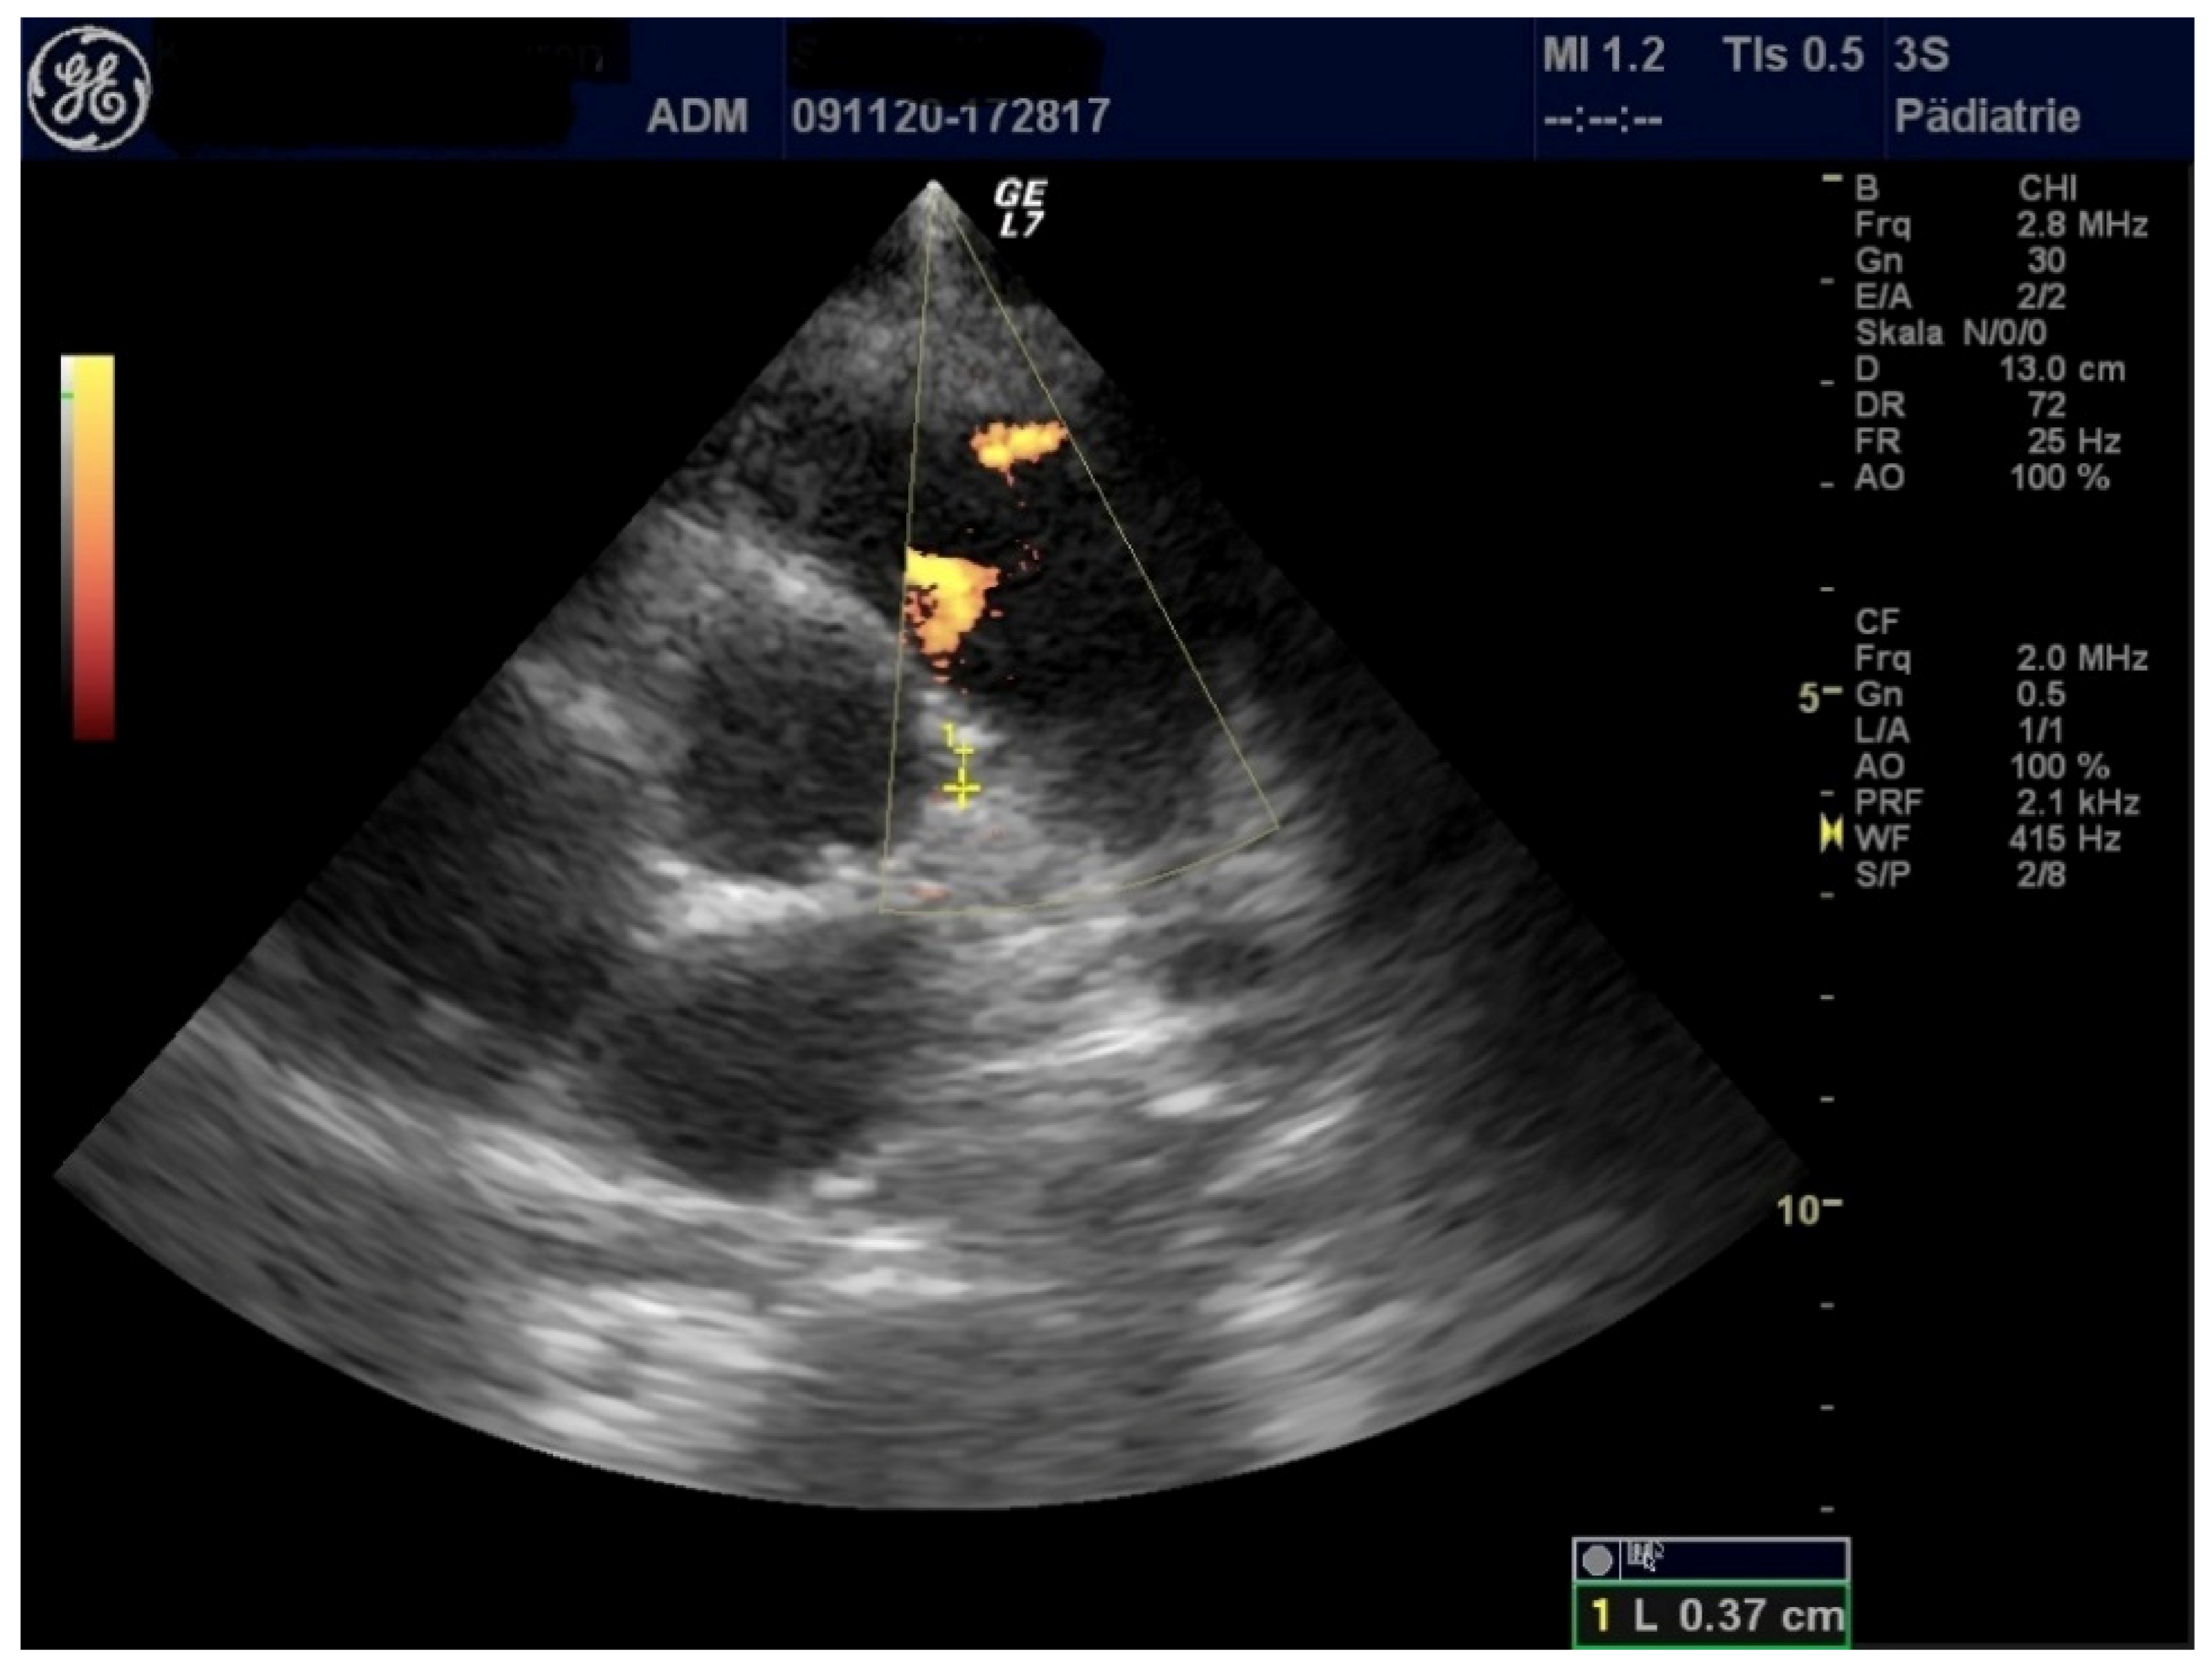

| LVEF (%) | 71 | 44 | 53 |

| FS (%) | 40 | 21.1 | 26.6 |

| MAPSE (cm) | 1.97 | 1.42 | 0.91 |

| TAPSE (cm) | 2.55 | 2.08 | 1.14 |

| LCA (mm) | 3.8 | 3.3 | 3.1 |

| RCA (mm) | 3.2 | 4.0 | 2.8 |

| Pericardial effusion (mm) | 7 | 3 | 5 |

| Pleural effusion (mm) | 9 (left), right 0 | 0 | 0 |